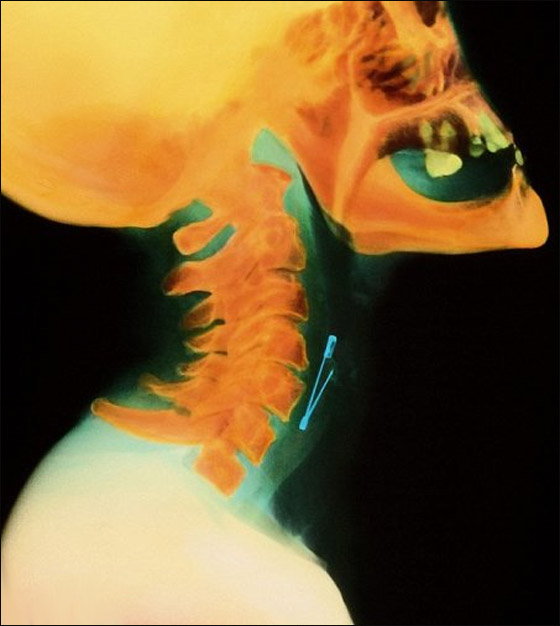

وقد تجعلك صورة الأشعة السينية الملونة للدبوس ومعها منظومة من الصور تهرش رأسك وأنت تتساءل: لماذا يلجأ بعض الناس إلى ابتلاع أي شيء آخر غير الطعام؟

دبوس الأمان يستقر في مريء امرأة